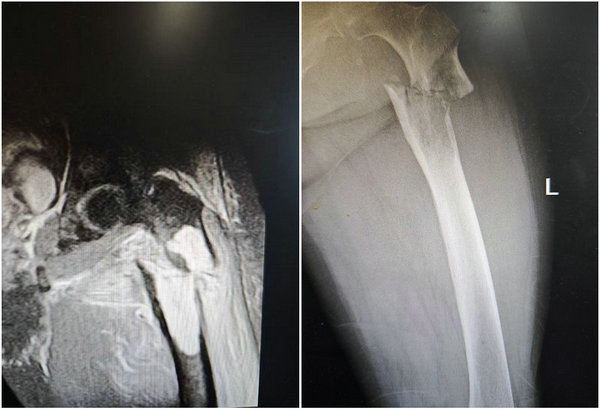

术前核磁及放射线影像

入院后,针对目前徐大娘的特殊病情及早起下地行走,避免长时间卧床的诉求,骨外科四病区副主任/医疗组组长李烁主任对患者进行了详细的问诊、查体并进一步完善辅助检查,明确了左股骨近端病理性骨折的诊断,科室主任李宝权组织了详细缜密的病情分析和充分的术前讨论后制定手术方案:行肿瘤骨整段切除并予肿瘤型假体人工股骨头置换。

术后影像